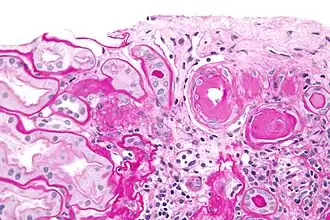

Micrograph showing renal arterial hyalinosis – pink ring right-of-centre. PAS stain.

In the kidneys, as a result of benign arterial hypertension, hyaline (pink, amorphous, homogeneous material) accumulates in the walls of small arteries and arterioles, producing the thickening of their walls and the narrowing of the arterial openings, a process known as arteriolosclerosis. The resulting inadequate blood flow produces tubular atrophy, interstitial fibrosis, and glomerular alterations (smaller glomeruli with different degrees of hyalinization – from mild to sclerosis of glomeruli) and scarring around the glomeruli (periglomerular fibrosis). In advanced stages, kidney failure will occur. Functional nephrons[6] have dilated tubules, often with hyaline casts in the opening of the tubules. Additional complications often associated with hypertensive nephropathy include glomerular damage resulting in protein and blood in the urine.

Histology

In benign nephrosclerosis, the changes occurring are gradual and progressive, however, there can be sufficient kidney reserve capacity to maintain adequate kidney function for many years.[10] The large renal arteries exhibit intimal thickening, medial hypertrophy, duplication of the elastic layer. The changes in small arterioles include hyaline arteriolosclerosis (deposition of hyaline, collagenous material), which causes glomerular collapse (wrinkling and thickening of capillary basement membranes and collapse of capillary lumen) and solidification (glomeruli exhibit sclerosis and increase in mesangial matrix). The degree of scarring correlates with the degree of glomerular filtration deficit.